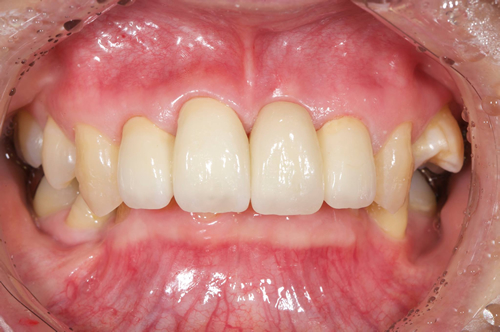

< 症例1 >

- 治療期間:6ヶ月

- 治療回数:8回

- 治療歯数:1歯

- 費用:インプラント治療:45万円 上部セラミック:89,000円

- リスク:メンテナンスを怠ると、インプラント周囲炎になる可能性があります。

- インプラント手術には合併症が伴う場合があります。

- 治療期間は治癒の状態により前後する場合があります。